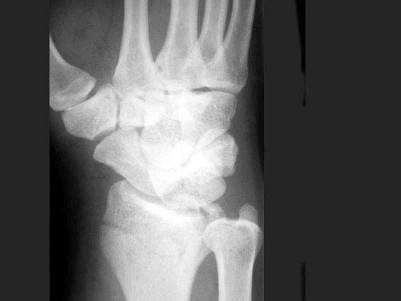

问题 男,22岁,滑冰时摔倒右手撑地时受伤,结合CR片,最可能的诊断是?(?)

选项 A.柯莱斯骨折 B.蒙泰贾骨折 C.加莱阿齐骨折 D.桡骨远端骨折 E.反柯莱斯骨折

答案 D